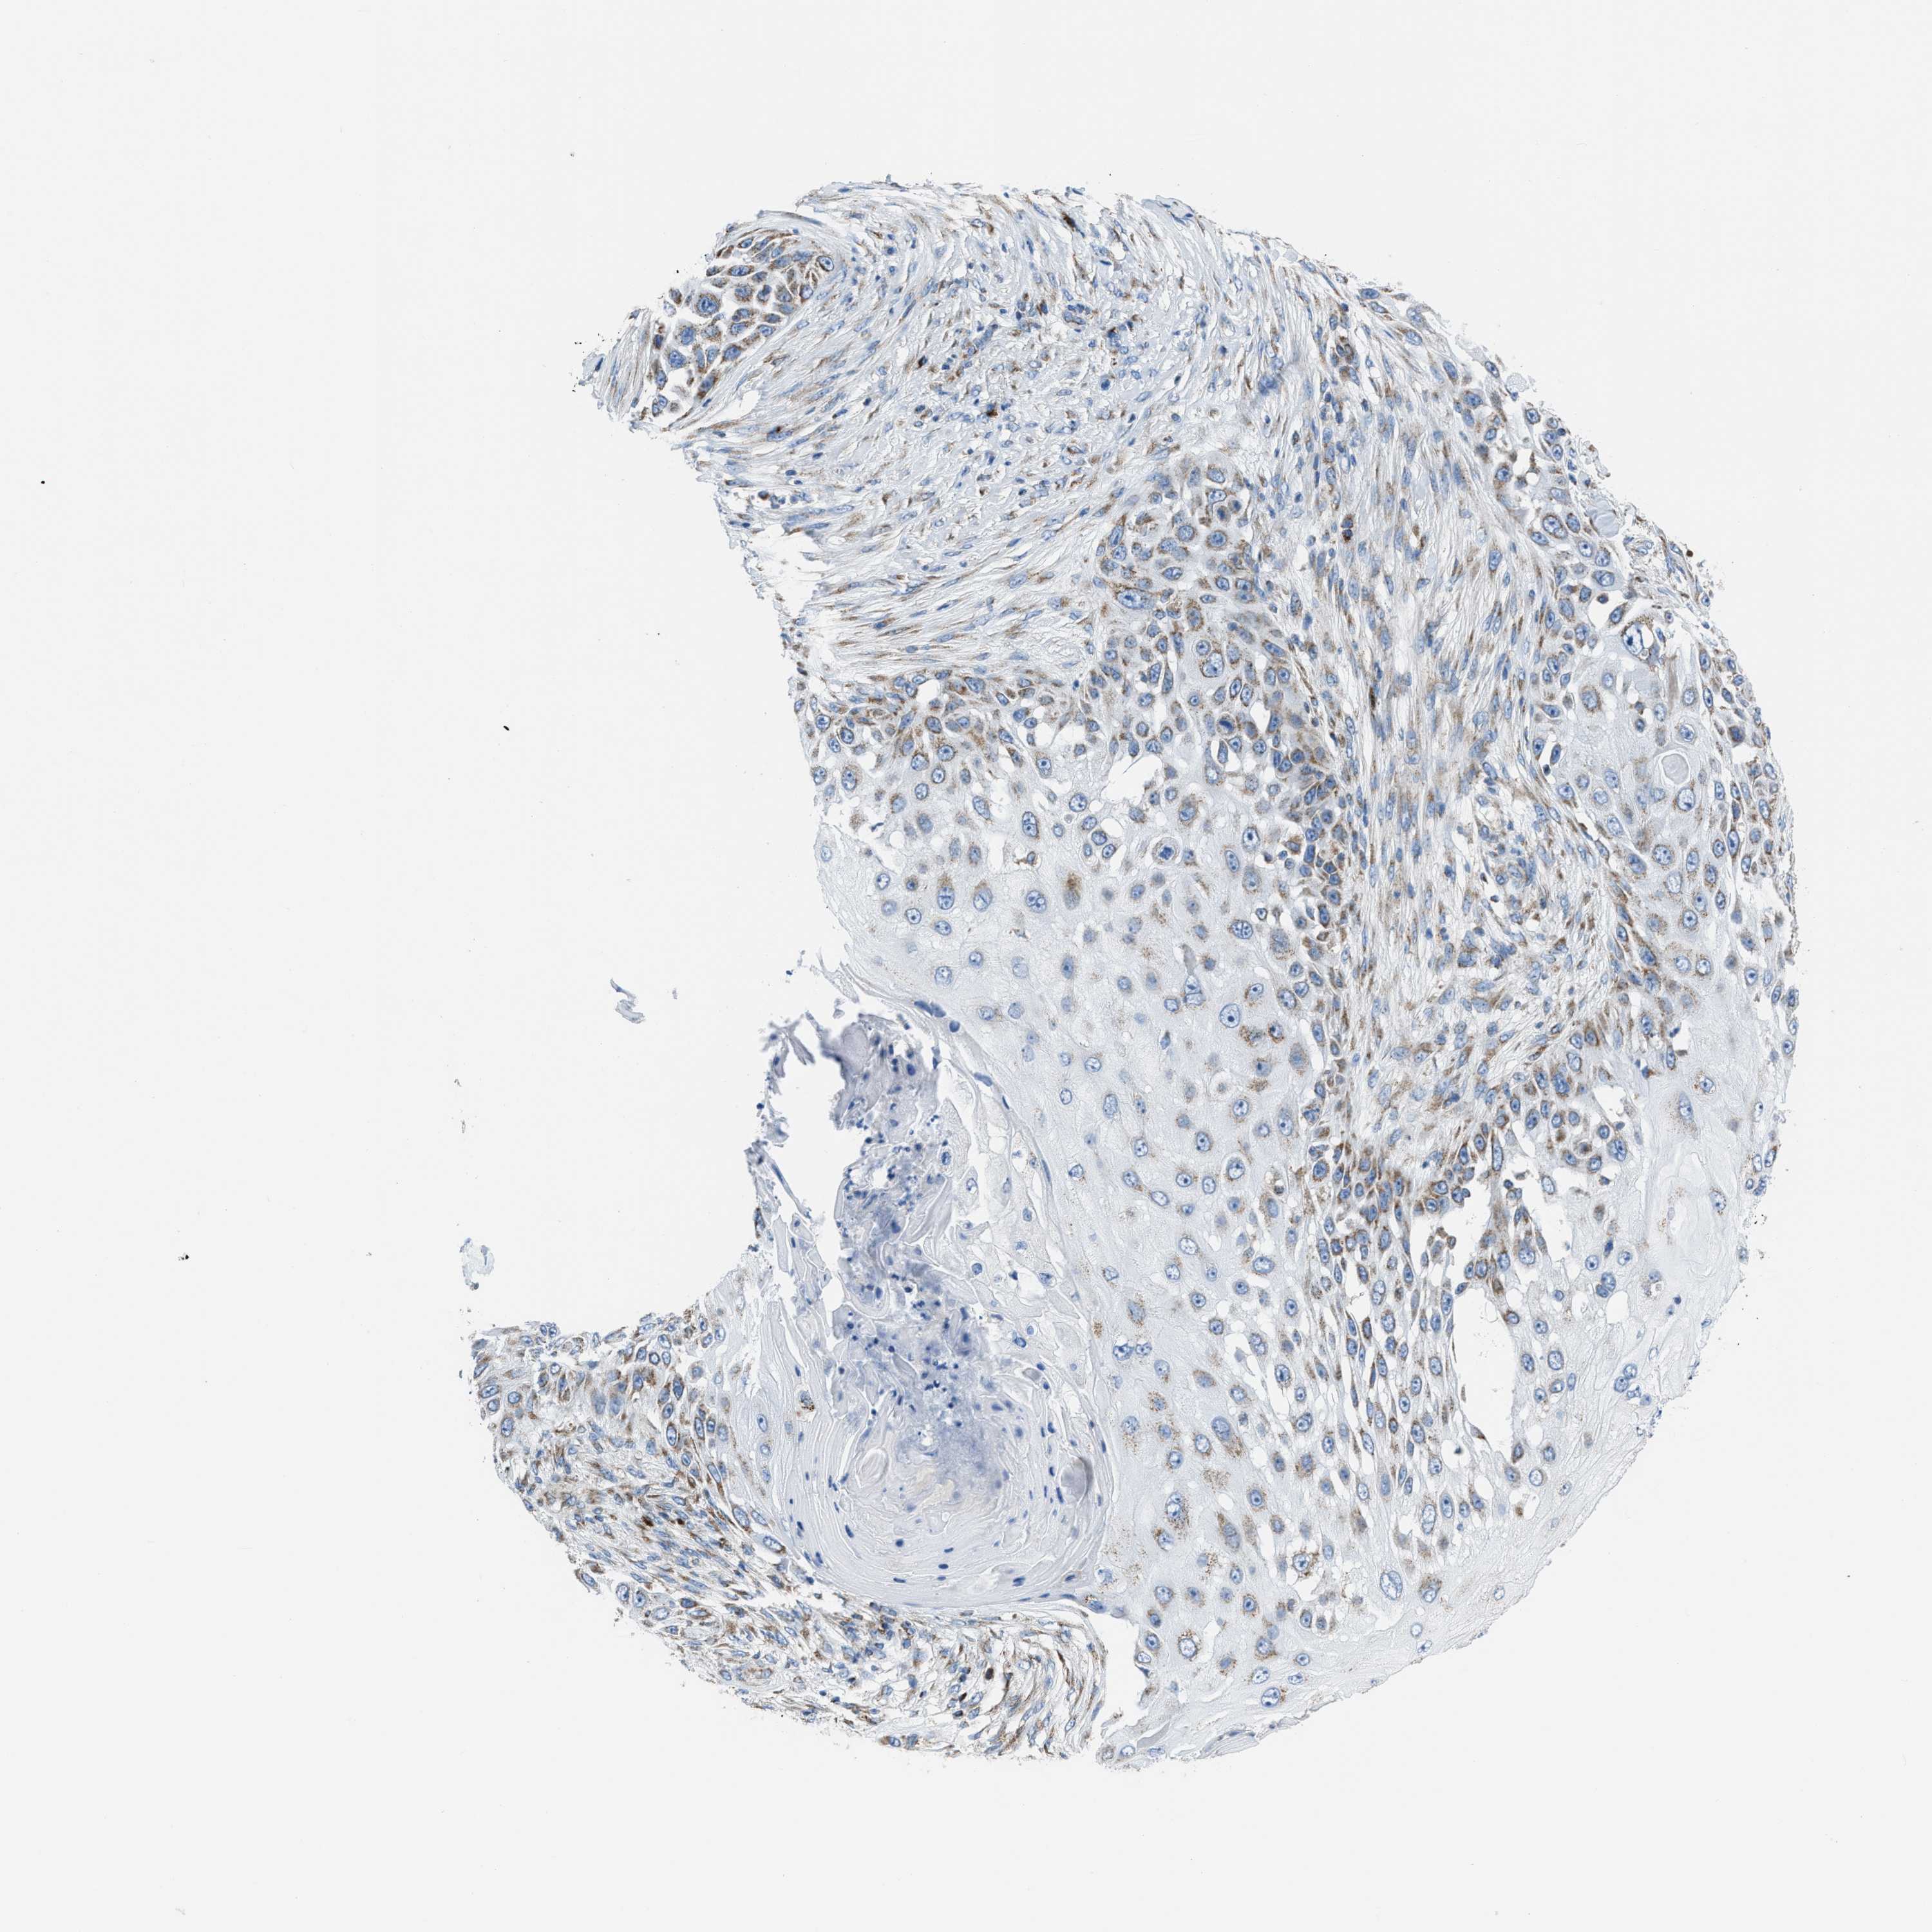

SKIN CANCER - Protein expressioni

A mouse-over function shows sample information and annotation data. Click on an image to view it in a full screen mode. Samples can be filtered based on level of antibody staining by selecting one or several of the following categories: high, medium, low and not detected. The assay and annotation is described here.

Each image is clickable and will lead to virtual microscopy that enables deeper exploration of all samples and also displays staining intensity scores, fraction scores and subcellular localization as well as patient and tissue information for each sample.

Antibody HPA018923

Squamous cell carcinoma, NOS